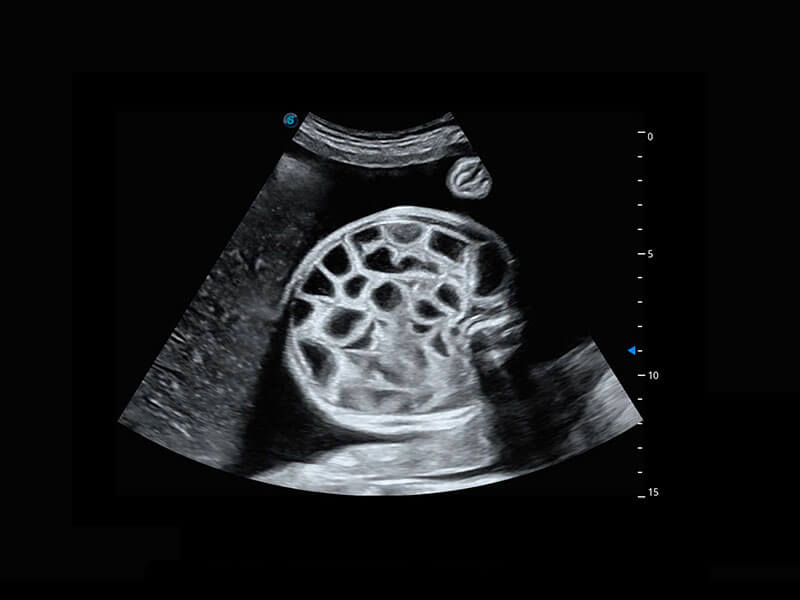

腔內(nèi)三維-宮內(nèi)節(jié)育器

腔內(nèi)三維-光影成像